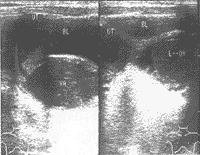

子宮和陰道畸形